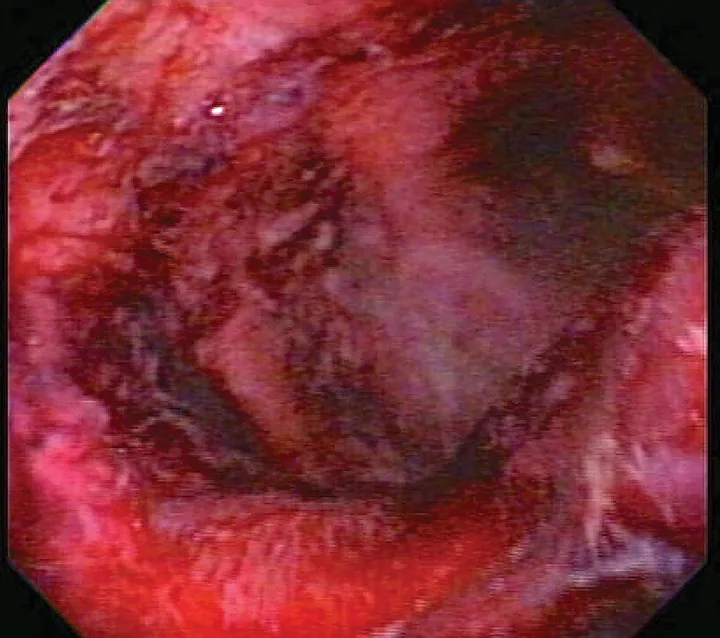

Critically ill patients are susceptible to GI ulceration (Figure 2) because of many factors, including primary or secondary GI disease, surgery, hypoperfusion, and mechanical ventilation. These patients also often require corticosteroids or NSAIDs because of inflammation, pain, and adrenal or immune-mediated disease. Ulceration can result in GI dysfunction, hemorrhage, and/or perforation.

FIGURE 2

Endoscopic image of duodenal ulcers in a critically ill patient

Corticosteroids and NSAIDs typically should not be used together, as their combined actions are likely to cause severe GI ulceration. Corticosteroids exert their anti-inflammatory effect in part through inhibition of several enzymes in the arachidonic acid cascade (eg, phospholipase A2, cyclooxygenase); NSAIDs also inhibit cyclooxygenases.14 The arachidonic acid cascade is important for maintaining normal GI mucosa and renal perfusion. Inhibition of prostaglandin production results in poor GI blood flow and poor mucosal barrier function, exposing the mucosa to the low pH of gastric acid and causing development (and poor healing) of gastric and intestinal ulcers.15,16